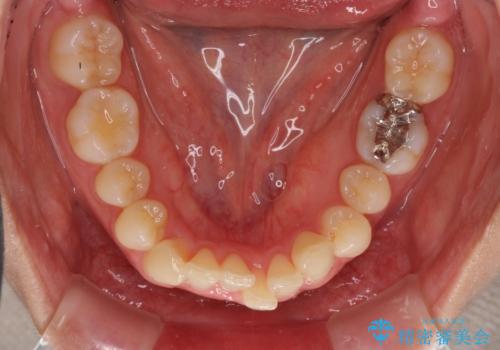

インビザラインによるディープバイトの改善

- 口元の前突感と深い咬み合わせ(ディープバイト)を気にして来院された患者様です。

インビザラインによる上下歯列の遠心移動(後方移動)と、それに伴う近心傾斜(前方傾斜)の改善により、口元の突出感とディープバイトを改善することとしました。

前歯のデコボコを最も気にしていましたが、咬み合わせが深く歯ぎしりが自由にできない点を指摘すると、常に食いしばってしまうことも悩みであることが分かりました。

咬合状態が大きく変化したため、治療後半では咬み合わせの位置が定まらなくなりました。上下の前歯に後戻り防止用のワイヤーを装着し、奥歯の咬合をフリーにしたことで1ヶ月ほどで咬み合わせが定まりました。